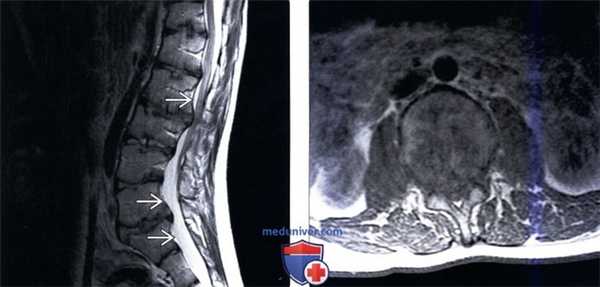

(Слева) Т2-ВИ, сагиттальная проекция (гомоцистеинурия): относительное незначительное ремоделирование позвонков на фоне дисплазии твердой мозговой оболочки, а также выраженные дегенеративные изменения межпозвонковых дисков, являющиеся причиной значимого стеноза спинномозгового канала.

(Справа) Аксиальное Т1-ВИ (гомоцистеинурия): на уровне межпозвонкового диска определяется выраженный стеноз спинномозгового канала на фоне дегенеративных изменений, которые нивелируют эффекты дисплазии твердой мозговой оболочки, приводящей обычно к увеличению размеров канала.